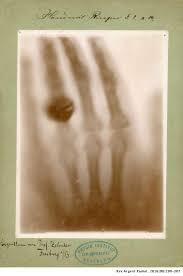

Entre los meses de septiembre y noviembre, Wilhelm Conrad Roentgen se encontraba estudiando los fascinantes rayos catódicos en su rústico laboratorio.

El 22 de diciembre logró obtener la primera radiografía de una persona: la mano de su esposa Bertha.